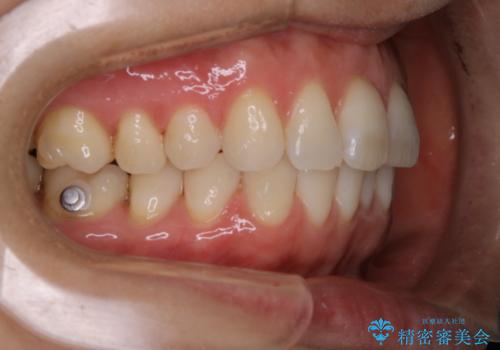

- インビザライン矯正治療中にステインが気になるとのことで来院されました。全体的にステインが付着していたため自費クリーニングPMTC(60分コース)を行いました。

インビザライン矯正治療中は、ご自身の歯にアタッチメントという突起物(効率的に歯の移動を行うため)をつけます。そのため、通常時よりもステインが付きやすい状態になることがあります。